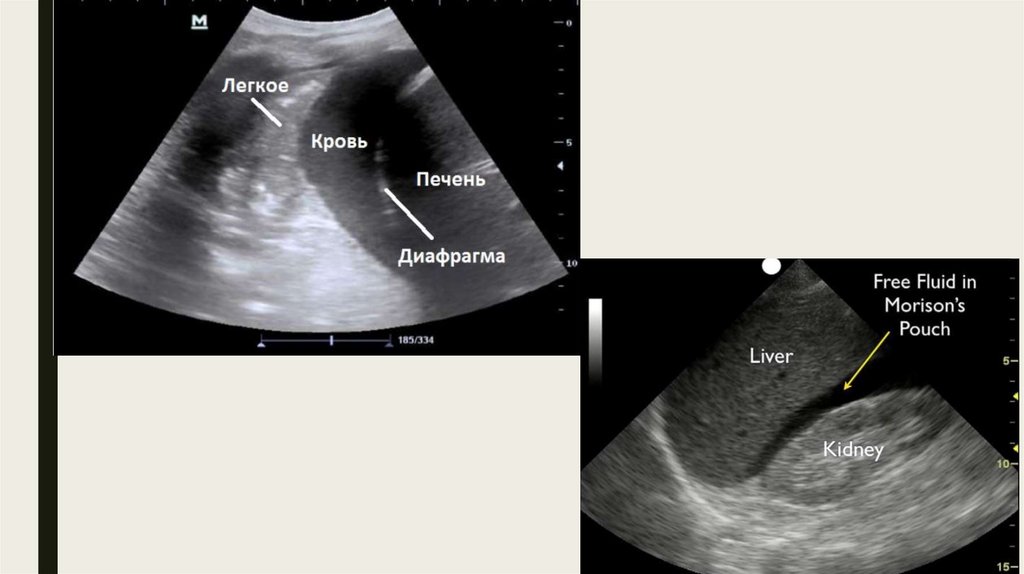

Правый верхний карман

Левый верхний квадрант